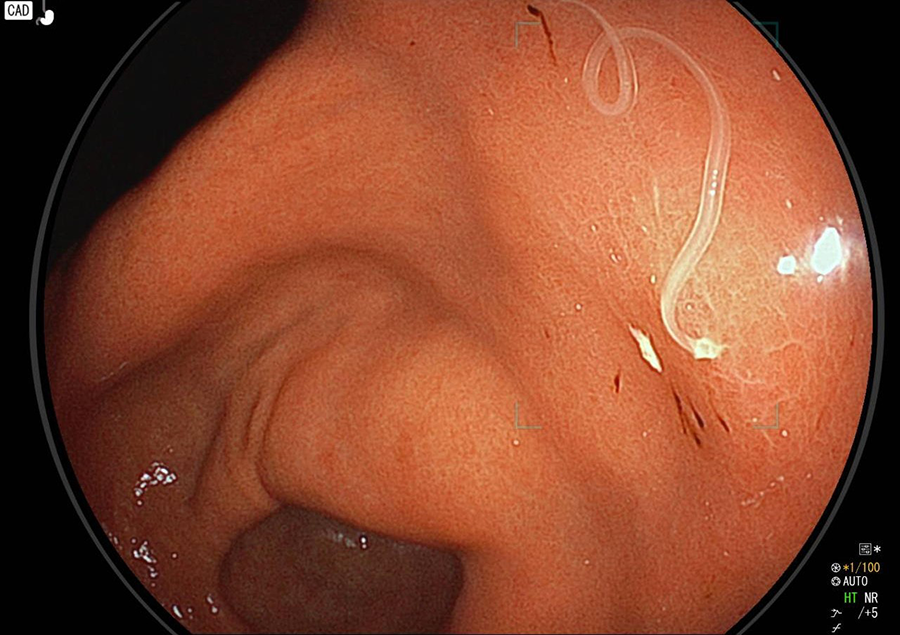

胃カメラ検査では、口又は鼻から内視鏡を挿入し、食道・胃・十二指腸の一部を観察します。直接胃や食道の粘膜を観察することができるので、色調や微妙な凹凸の変化が分かり、潰瘍・炎症・ポリープ・腫瘍などの診断が可能です。

胃カメラでわかる病気/病変

- 胃アニサキス症